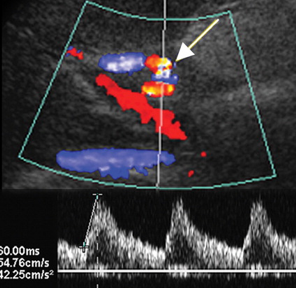

hepatic artery stenosis (HAS)